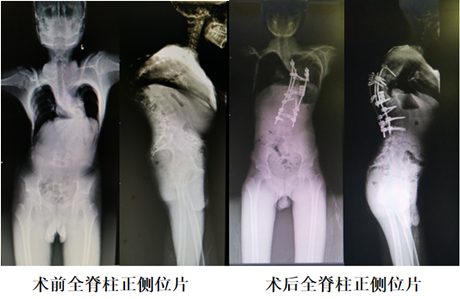

经过多学科会诊和脊柱外科全体专家讨论后,团队制定了详尽而周密的治疗计划。首先利用患儿的脊柱3D打印模型进行手术模拟,确定了截骨范围及复位方案,最终选择了截骨范围为T10-T12,并利用人工椎体做支撑,在牵引下复位脊柱。确定手术方案后,3月10日,由邓幼文教授、周勇副教授,王正光主治医师、刘仁峰总住院医师组成的手术医师团队,为小袁实施了后入路脊柱后凸畸形矫形手术。术后生命体征平稳,脊柱序列恢复较满意,身高增高了近10公分。目前小袁,已顺利出院。